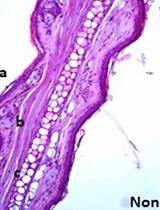

Notably, different species of malaria parasites have different predilections for different types of red blood cells. P. chabaudi AS parasites display a preference for normocytes, whereas P. berghei ANKA parasites display a preference towards reticulocytes (Sinden et al., 2002). This is most apparent during early infection when parasite numbers are low. At higher loads, parasites tend to be found in all erythrocyte stages. Parasites also differ in other properties with which the researcher should become familiar. For example, P. chabaudi AS parasites cytoadhere, and as a result, ring-stage trophozoites are the main lifecycle stage observed on smears. P. berghei ANKA parasites do not cytoadhere; therefore, all life cycle stages are observed on smears. Our standard practice is to count all stages toward an aggregate parasitemia value; in some cases, it may be preferable to count lifecycle stages separately. See Figure 2 for images of the primary blood stages of Plasmodium parasites.

Figure 2. The major Plasmodium life cycle stages observed in blood. Example images of ring trophozoites (commonly referred to as “rings”), late stage trophozoites, and very late stage schizonts are shown. Note that the schizonts in these images have segmented into individual merozoites, which immediately precedes parasite egress. All images are P. berghei ANKA; P. chabaudi AS rings have a similar appearance to P. berghei ANKA rings.